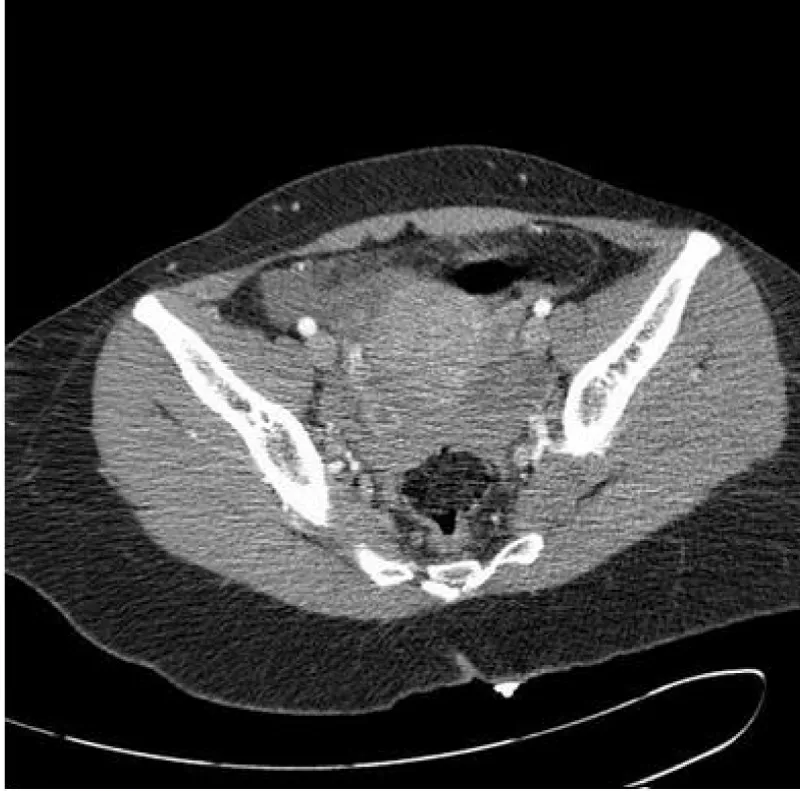

A 29-year-old female presented to a Level I Trauma Center after sustaining multiple stab wounds to the top of the head, right chest, and right upper quadrant of the abdomen. After initial stabilization, skull films (anterior and lateral films) showed a knife blade lodged inside her skull (Figure 1, arrow).Patient had altered mental status on admission with a GCS of 12 and a right upper extremity hemiparesis. Computed tomographic scan of the chest and abdomen revealed right apical pneumothorax, blood in Morrison’s pouch (Figure 2, arrow), and pelvic hemorrhage (Figure 3). She was taken to the operating room by the trauma and neurosurgery teams for simultaneous procedures including craniotomy with en-block removal of the knife blade and an exploratory laparotomy, cholecystectomy, right tube thoracostomy, and hemostatic control of a grade 2 liver laceration in segment V. The bed/operating table was turned sideways with middle of the operating table across from the anaesthesia machine and the head pointed into the room. The Trauma Surgery team was positioned below the ventilator circuit and the Neurosurgery team above. Two separate operating room set ups were used by the operative teams. The patient was placed in a supine position on the operating table for both procedures. The simultaneous operations lasted approximately two hours. There were not any operative complications or any problems between the trauma and neurosurgery teams.